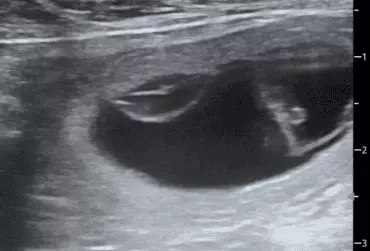

W literaturze opisano niewiele przypadków ciąż bliźniaczych jednokosmówkowych u suk. W trakcie wczesnej diagnostyki ultrasonograficznej ciąży u suki rasy whippet (chart angielski) zobrazowano pęcherz ciążowy, w którym znajdowały się dwa zarodki. Podczas badań kontrol­nych zarodki, a później płody wykazywały prawidłową organogenezę i żywotność. Ich rozwój przebiegał podobnie względem pozostałych ośmiu płodów. W 63. dniu ciąży wykonano zabieg cesarskiego cięcia i wydobyto dwa płody tej samej płci, o bardzo podobnym wyglądzie, z dwóch pęcherzy płodowych przyczepionych do jednego łożyska, oraz pozostałe osiem płodów.